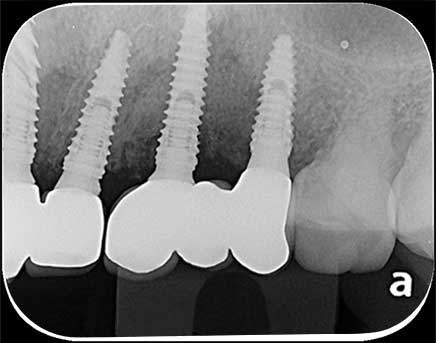

案例2